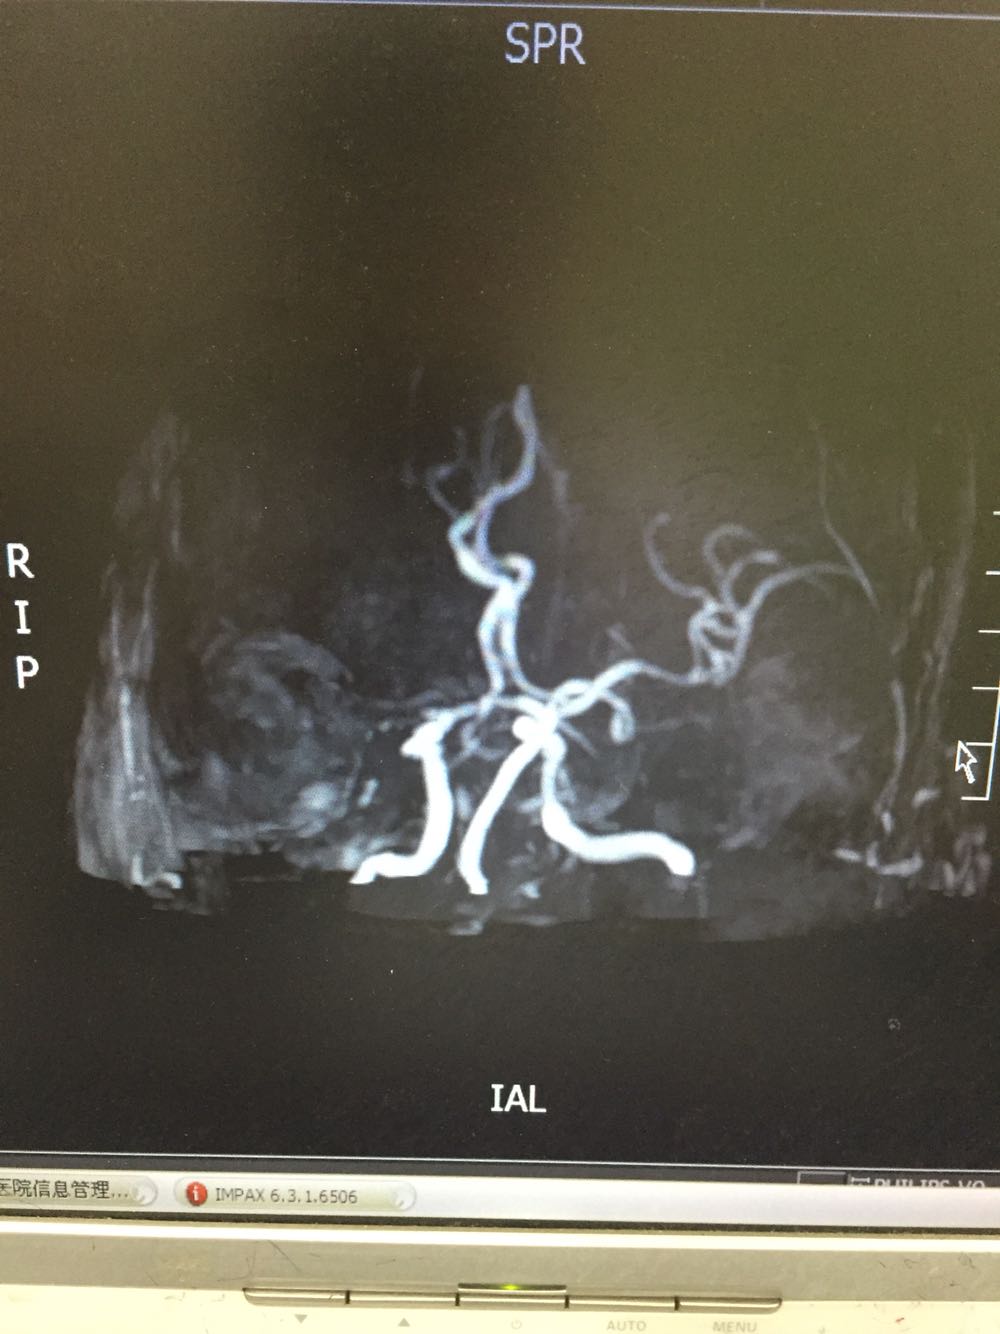

患者入院治疗后症状一度好转,左侧肢体肌力3级+,于入院后第二日病情突然加重,伴意识障碍,头DWI示:脑梗死伴脑出血 右侧大脑中动脉闭塞。停止当前治疗方案,脱水脑保护,营养神经对症治疗。入院后第5日复查头CT示:右侧大面积脑梗死,脑出血吸收期,伴左侧枕叶脑出血。患者左侧枕叶脑出血不好解释,能否是搬运及护理时外伤所致?